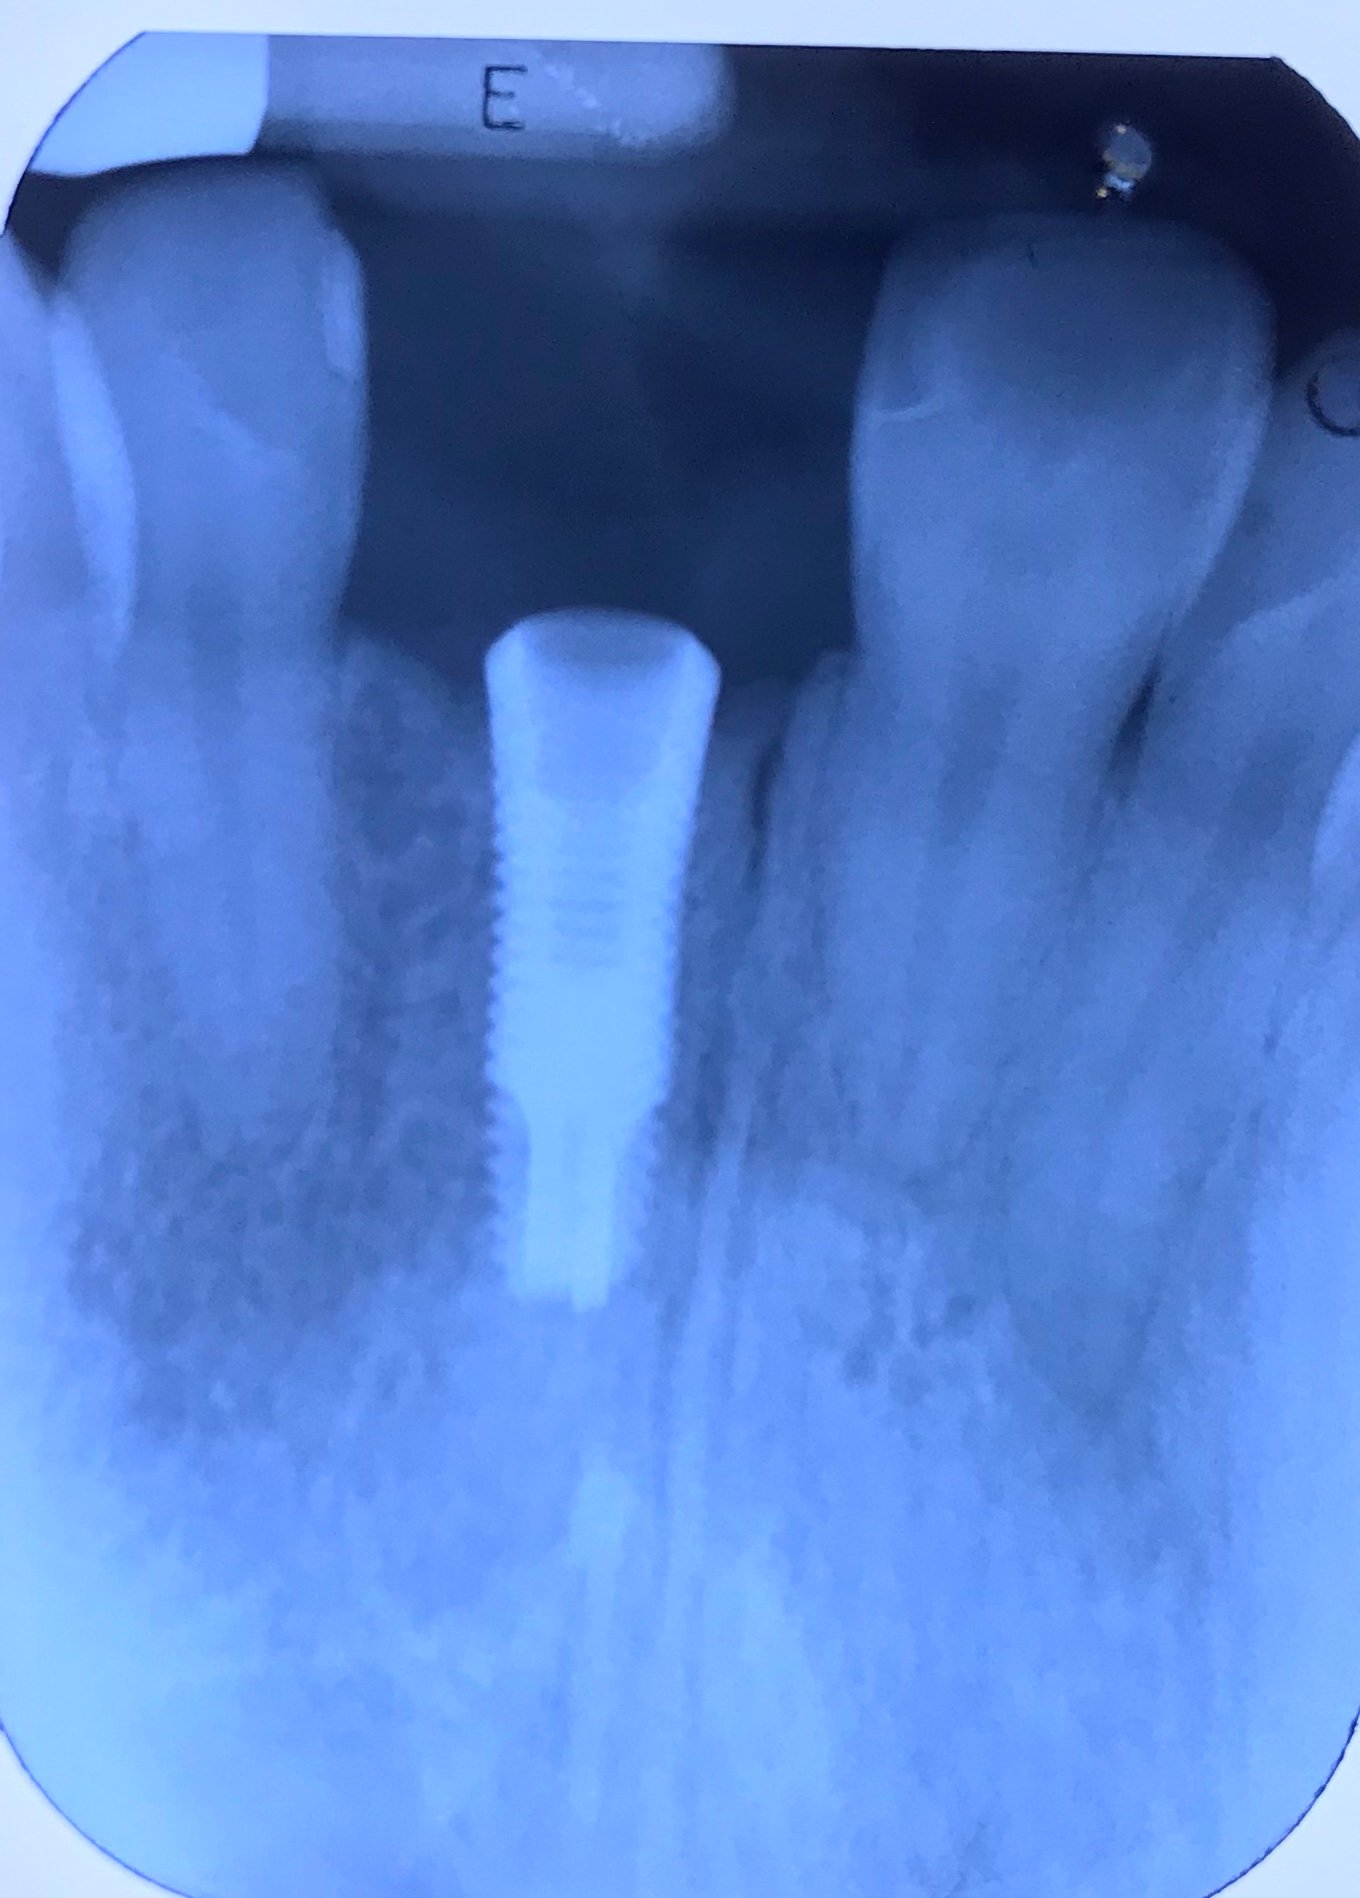

Necesito saber q implante es el #21 por favor